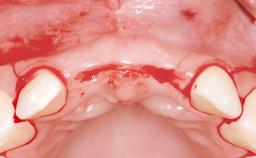

In 2001, a 48-year-old woman presented at a dental clinic with a failing fixed partial denture spanning from teeth 13 to 21. She was experiencing pain upon function, tenderness to palpation facial to tooth 13, and severe mobility of the prosthesis. Radiographic and clinical assessment revealed a subcrestal fracture of tooth 13, making its restoration unlikely. It was determined by the clinician that the tooth needed to be extracted prior to proceeding any further with dental care. After the extraction, the patient lost confidence in the progression of her treatment and sought consultation at the Center for Implant Dentistry. At her consultation visit in our clinic, an extra- and intraoral clinical examination revealed a medium lip line at full smile and an edentulous area spanning from 13 to 12 with both vertical and horizontal deficits in hard and soft tissue.

Bone Augmentation Horizontal|Staged|Vertical

Augmentation Materials Autogenous chips|Autogenous block(s)|Membrane